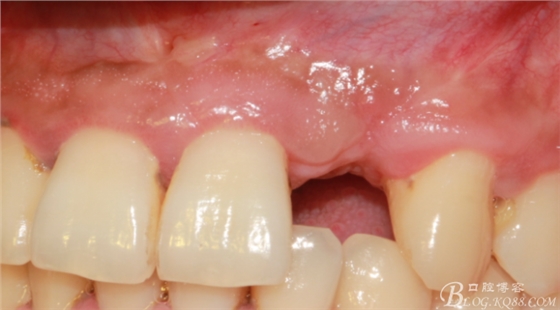

10天拆線一切正常,又過了兩周患者復(fù)診,自述期間無異常。口內(nèi)檢查,真的嚇了一跳,唇側(cè)鼓了個(gè)包,擠壓有白色分泌物溢出,絕對(duì)不是膿液,液體排除后,術(shù)區(qū)觸診空虛,外觀塌陷。這時(shí)候考研大夫的時(shí)刻到了,是先觀察一段時(shí)間再說?還是馬上進(jìn)行處理?我的回答是:馬上處理!如果你沒有及時(shí)處理,而是放患者回家觀察,那么接下來會(huì)發(fā)生如下情況:1.回家后患者家屬及親友會(huì)有很多你可以想象得到的討論;2.患者及家屬會(huì)對(duì)你產(chǎn)生不信任,勢(shì)必會(huì)到其他門診或醫(yī)院檢查,他院大夫會(huì)不會(huì)發(fā)表對(duì)你不利的言論;3甚至?xí)蚁嚓P(guān)法律界人士找你討要說法。